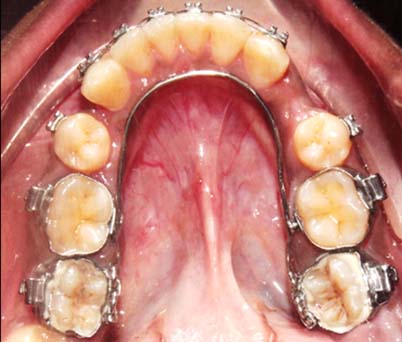

After one month of treatment, correction of the lingually tipped molar was noticed [Table/Fig-4a] along with the correction of the scissor bite [Table/Fig-4b]. Lower anterior crowding was also relieved and adequate alligment of the lower arch was noticed.

One month later: a) occlusal picture shows the correction of lingually tipped molars; (b) left lateral view showing the correction of scissor bite on left side.